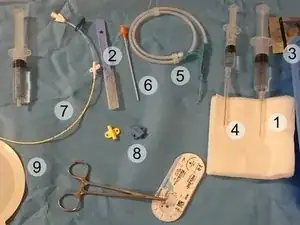

Clinical equipment refers to medical devices that are widely used in clinical settings for patient care. This includes devices like patient monitors, dialysis machines, ventilators, thermometers, stethoscopes, nebulizers, blood pressure monitors, etc.

Clinical equipment today is still a rapidly growing field. Modern advances seek to streamline medical procedures, reducing the likelihood of negative outcomes and furthering what is possible to treat. Specifically, the forefront of medical technology includes the implementation of robotics. For instance, robotic-assisted surgery systems, like da Vinci systems from Intuitive Surgical, aim to make surgery less invasive and less risky. Robotic-assisted surgery allows surgeons to be more precise and flexible than standard methods, potentially enabling medical professionals to invent surgical procedures that have never been possible before.